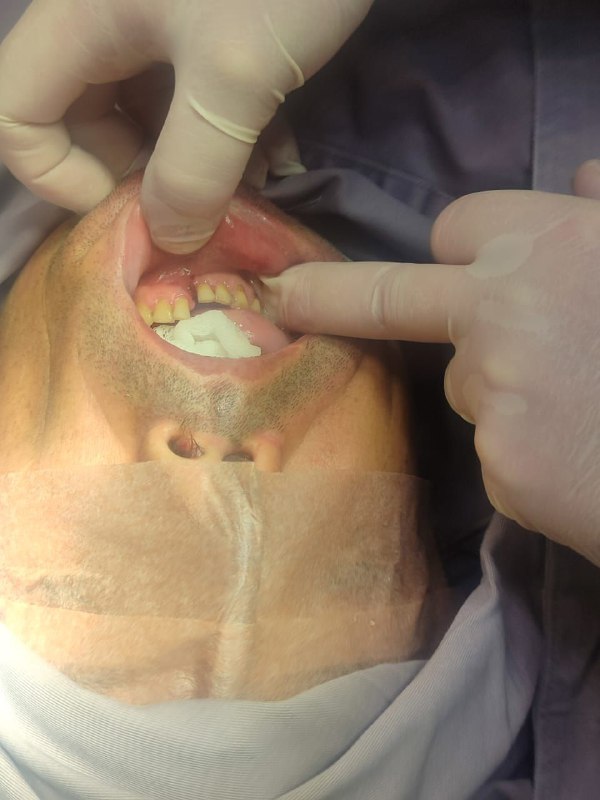

Fractura Facial por Accidente Automovilístico – Cirujano Maxilofacial La Paz (el alto) – Centro de Cirugía Bucal y Traumatología Maxilofacial en Bolivia

Los accidentes de tránsito son frecuentes y la falta de uso de cascos en motocicletas o cinturones de seguridad en automóviles incrementa el riesgo de fracturas faciales. En nuestro Centro de Cirugía Bucal y Traumatología Maxilofacial brindamos atención de emergencia inmediata y especializada. Consúltenos.